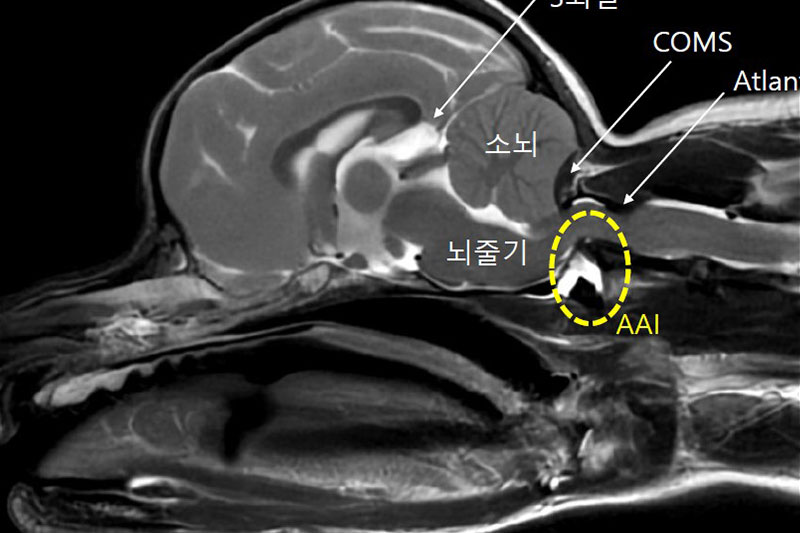

본 병원은 GE사의 1.5T 고해상도 자기공명영상장치(MRI)를 이용하여, 자기장을 이용한 비침습적 방식으로 뇌, 척수, 근골격계 등 다양한 연부조직을 정밀하게 영상화할 수 있습니다. MRI는 방사선을 사용하지 않아 반복 촬영에도 안전하며, 신경계 및 연부조직에 대한 탁월한 해상도를 제공하여 정확한 진단에 매우 유용합니다.

또한 본원의 MRI 장비는 GE사의 PROPELLER 기법을 도입하여 호흡이나 움직임에 따른 영상 왜곡을 최소화하면서도 검사 시간을 단축시켜, AI 기반 영상 처리 기술을 통해 노이즈를 줄이고 더욱 선명하고 명확한 영상을 획득할 수 있습니다. 이러한 기술적 강점을 바탕으로 마취 시간과 그에 따른 환자의 부담을 줄이면서도, 진단에 충분한 고화질 영상을 안정적으로 확보할 수 있습니다.